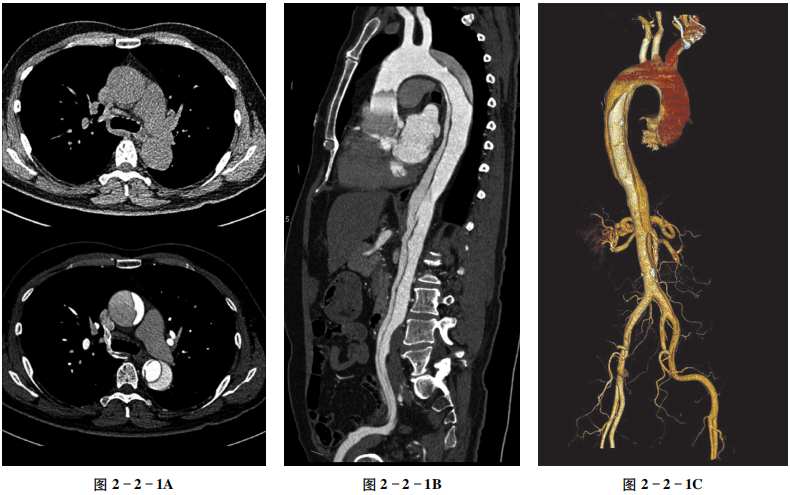

主动脉夹层诊断依赖于影像学检查,特别是主动脉CTA检查,是诊断主动脉夹层的金标准。